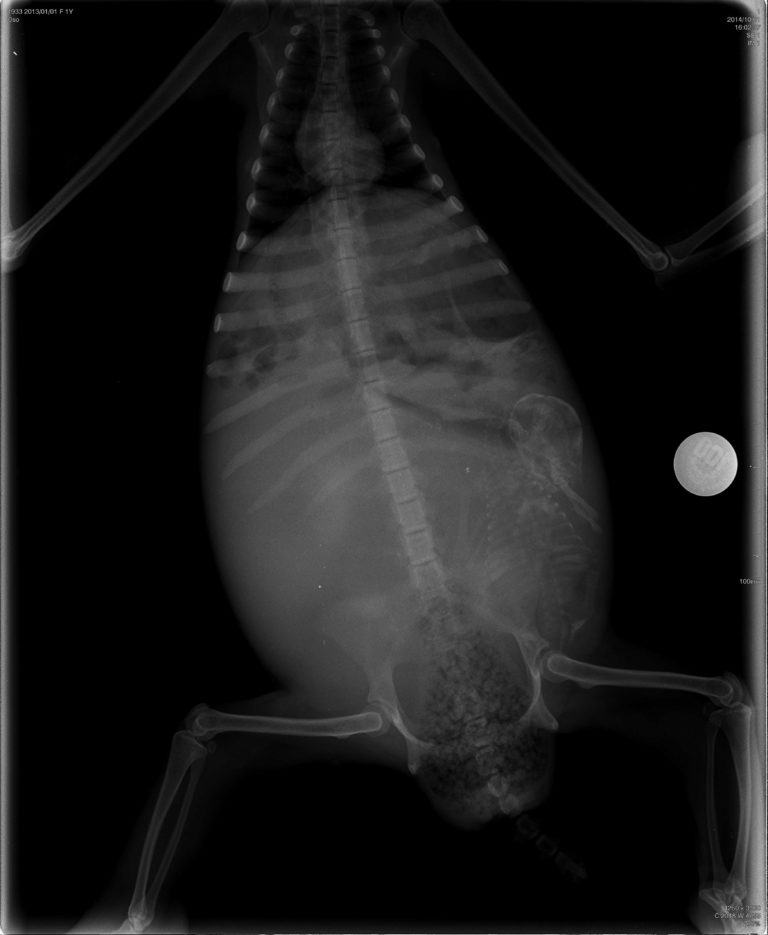

We arrived at Veterinarian Yesse Alpizar, in Herradura. I’ve taken other patients to Yesse before. She is one of the kindest and smartest vets I’ve met and she also happens to have a clinic equipped with a digital X-ray and ultrasound machine. After getting a complete history on momma sloth, Yesse examined her and agreed with me that she was in labor. We first took an X-ray. It was amazing to see the little life inside of mom’s belly…but unfortunately the baby was in a breech position and mom was completely full of urine and feces (sloths can hold up to 30% of their body weight in urine/feces) meaning that the baby changing position wasn’t likely. At this point, c-section was discussed but we needed to check the baby with an ultrasound to confirm a heartbeat and the exact position. With the first swipe of the ultrasound probe, we didn’t see a heartbeat. My heart sank. Just one day before I had felt the baby move inside of mom’s belly. So I knew that recently it was alive and I could only hope that it still was. Yesse kept swiping the probe around mom’s belly searching and searching for a tiny flicker of the heart. Was the baby still alive?!?